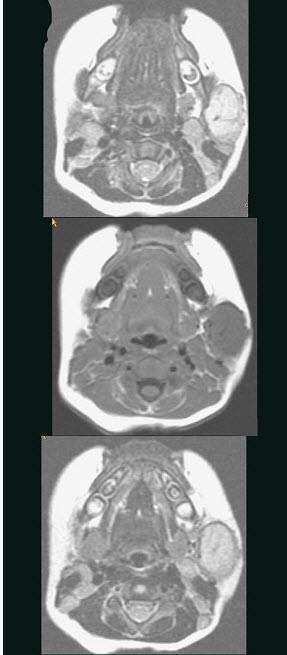

40岁,患者,左面部渐进性增大的包块,MRI检查如图所示,应考虑为()。

A、左面部毛细血管瘤

B、左面部囊肿

C、左面部脓肿

D、左面部脂肪瘤

E、左面部神经纤维瘤

A